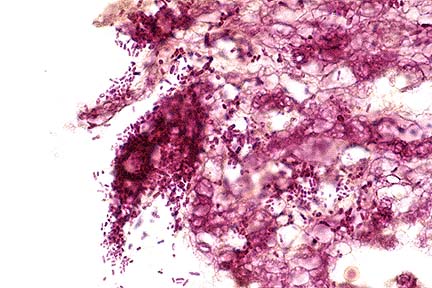

Dermal eosinophilic granuloma with cross sections of Habronema remnants from the pastern of a horse. (HE, 100X, 81K)

Higher magnification of the eosinophilic granuloma containing larval remnants of Habronema sp. shown above (HE, 400X, 37K)

Contributor's Diagnosis and Comments: Dermatitis, eosinophilic, granulomatous, ulcerative, fibrosing, locally extensive, severe with intralesional necrotic Habronema sp. larvae, skin of pastern.

Differential diagnosis also should include neoplasia such as sarcoid or squamous cell carcinoma as well as exuberant granulation tissue, fungal infection, and pythiosis. Cutaneous habronemiasis is induced by larvae of H. muscae, H. microstoma or Draschia megastoma at cutaneous and mucocutaneous sites. The larvae are transmitted to these sites by flies. Traditional sites for dermal reactions to occur are the ocular conjunctiva and the prepuce of the stallion. Histologically, aggregates of eosinophils, epithelioid macrophages and foreign-body giant cells typically react to the presence of Habronema larvae. Larvae or their remnants may be found embedded in some inflammatory reactions.

Histologically, lesions consist of a highly vascular granulation tissue with neutrophils and other inflammatory cells at the periphery and central aggregates of eosinophils. If larvae or larval remnants are present, they are surrounded by epithelioid macrophages, multinucleate giant cells, eosinophils, lymphocytes, and plasma cells (eosinophilic granulomas).